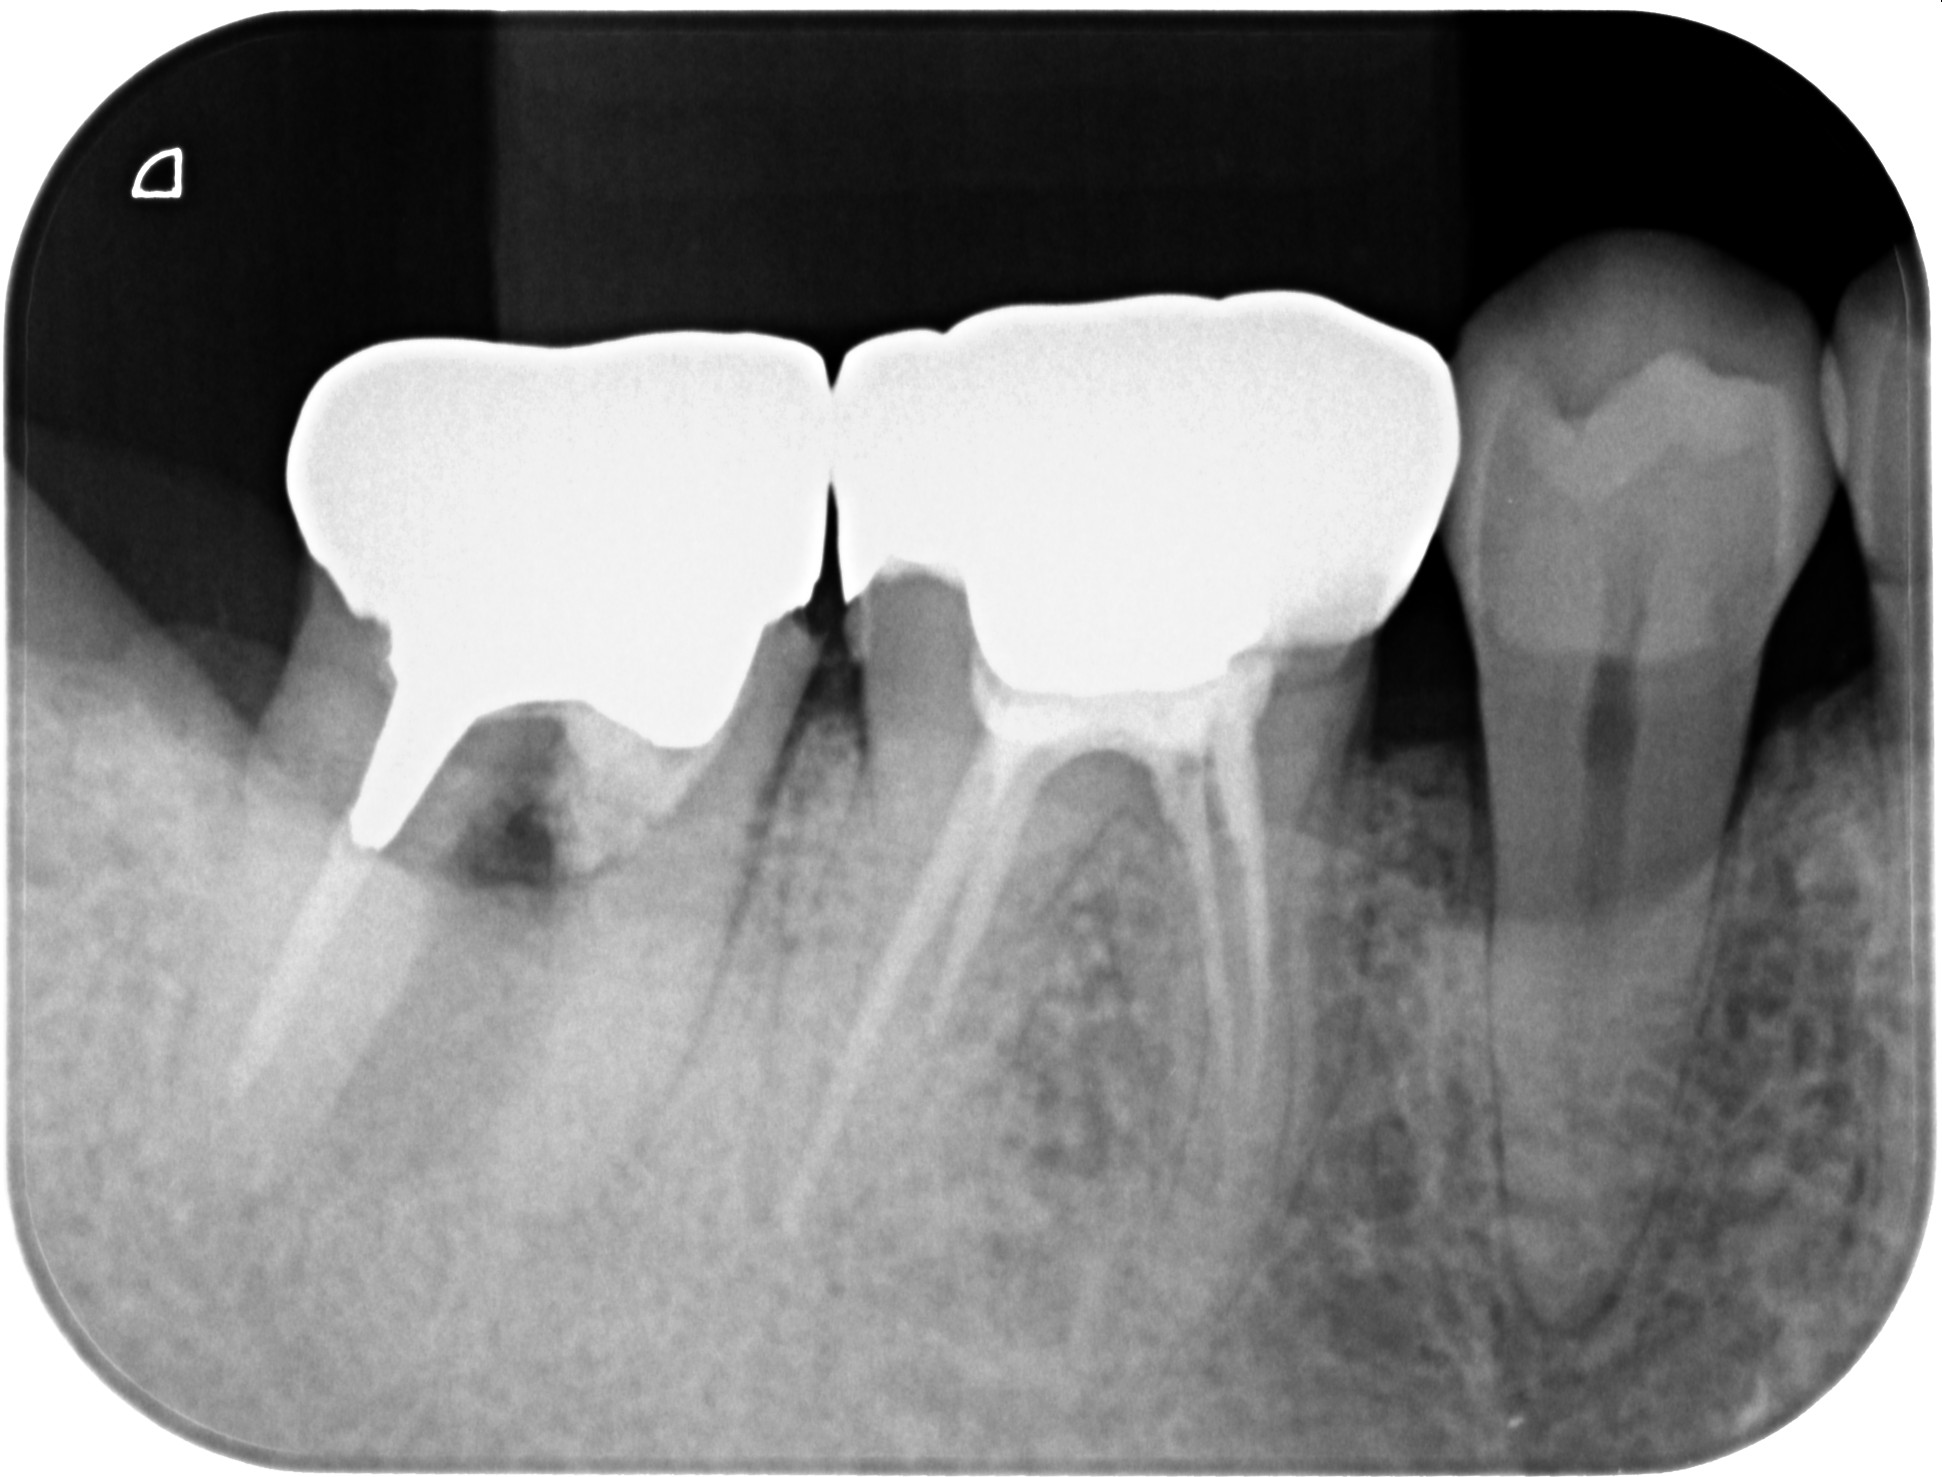

右下の奥歯が重度の歯周病による骨の吸収も進み始めていました。また、痛みを伴うようになってきたため、残念ながら抜歯となり、インプラントによる治療を行うこととなりました。

ソケットプリザベーション後、6ヶ月の治癒期間後にインプラントの埋入実施。

インプラント後、最終的な被せ物(ジルコニア)装着後のエックス線